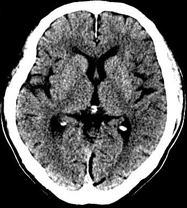

目前臨床對于16層CT的認可主要集中在三維成像領域上的突破.在16層CT的產品平臺上,常規(guī)掃描就能實現(xiàn)滿足三維成像的要求,因此16層也被稱為三維CT,三維成像給臨床診斷帶來了更精確更豐富的診斷信息,我們以臨床為例:

如上圖所示,相鄰的三張軸位圖像未見明顯異常,根據(jù)傳統(tǒng)軸位圖像很難得到準確的臨床診斷。

同一病人利用容積數(shù)據(jù)進行三維處理后,高品質MPR和三維圖像上則清晰顯示了縱向排列的腹腔干與腸系膜上動脈相鄰近,血管發(fā)生變 異,近端血管閉塞,為臨床提供了精確的診斷信息。

從上面的例子可以看到,能否為臨床提供高品質的三維影像成為了16層CT的核心價值,而東芝新一代的 全景三維16層CT擁有最為  先進的3項核心技術,在16層核心價值上的表現(xiàn)自然值得期待。